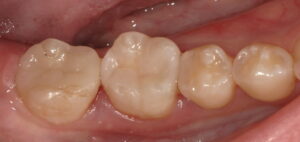

術後:ダイレクトボンディングで修復されています。

※手前の歯の溝に着色が無く、とても白い歯なのでステインは付けませんでした。ちなみに7番(一番左の歯)はセラミックインレーが入っております。

この方法だと必要以上に歯を削らなくて済みますので、術後に痛んだり凍みたりといったことがほとんど起こりません。歯の強度も保たれます。

治療回数:1回(約60分)

料金:¥55,000(税込)